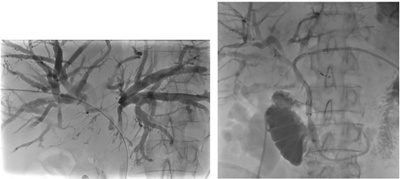

In den meisten Fällen ist es möglich mittels Endoskopie (endoskopische retrograde Cholangiopankreatikographie, ERCP) einen Aufstau der Gallenflüssigkeit durch Einlage eines Plastikröhrchens (Stent) zu behandeln, insbesondere wenn es sich um eine gutartige Ursache des Gallenaufstaus handelt. Mögliche Komplikation hierbei ist jedoch das Auftreten einer Bauchspeicheldrüsenentzündung (Pankreatitis). Bei tumorbedingtem Aufstau der Gallenflüssigkeit mag eine ERCP aufgrund der Verlegung des Gallengangs nicht gelingen. In solch einer Situation ist der technische Erfolg des interventionellen Verfahrens, der sog. perkutanen transhepatischen Cholangio-Drainage (PTCD), höher und birgt nicht das Risiko einer Pankreatitis. Hierbei wird zunächst in Lokalanästhesie ein erweiterter Gallenweg unter Ultraschall-Bildführung mit einer feinen Kanüle durch die Haut punktiert. Dann wird unter Röntgen-Kontrolle ein Draht bis in den Zwölffingerdarm vorgeführt über den schliesslich ein Metallgitterstent in den Hauptgauptgallengang eingebracht wird, um so den Aufstau der Gallenflüssigkeit zu beheben.

Wiederherstellung des Gallenabfluss bei einem Patienten mit einer Abflussstörung aufgrund einer zentralen Lebermetastase mittels perkutaner transhepatischer Cholangio-Drainage (PTCD).